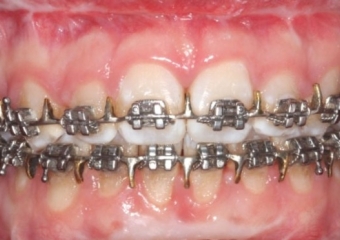

Mordida inicial